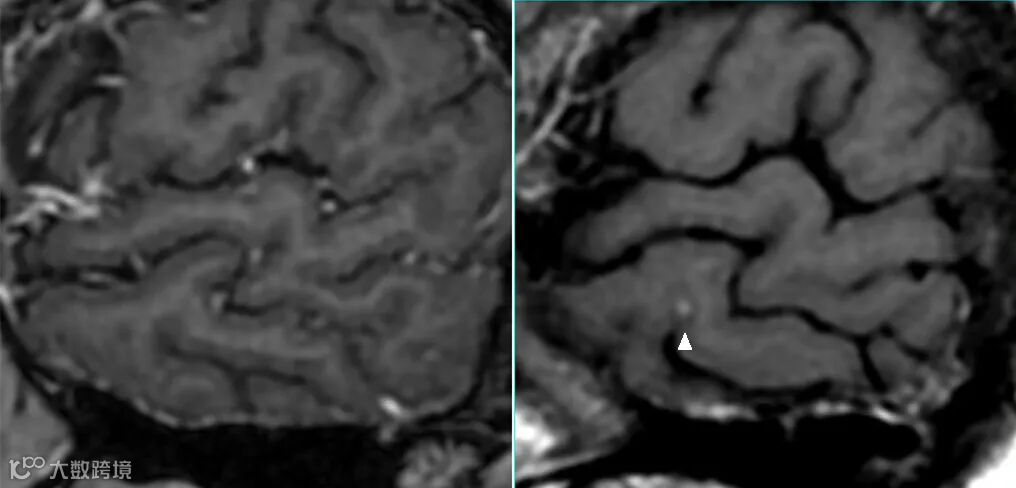

- 但该序列注射对比剂后,横、矢、冠三个方位上血管搏动伪影都非常大,并不利用血管层面及颅底区域病变的显示与判读。如上图△。

- 该序列较2D自旋回波序列,可在一定程度上改善血管搏动伪影。如上图△,该扰相梯度回波T1WI序列上并未见明显血管搏动伪影。